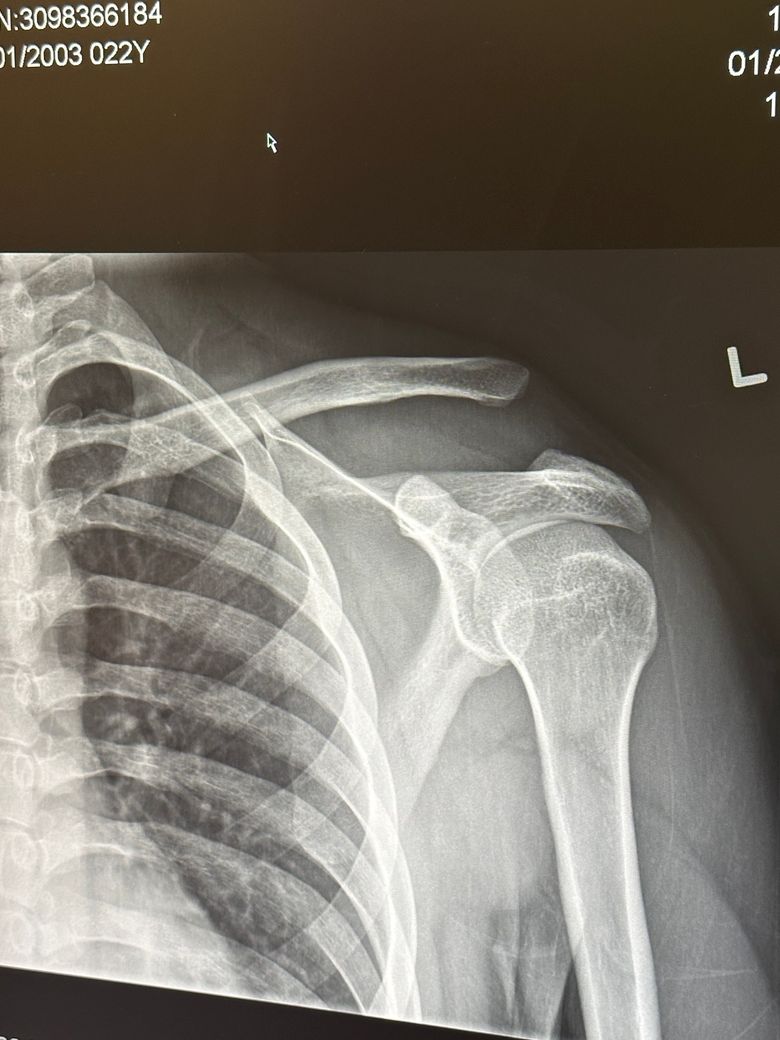

어깨 이거 문제 없이 괜찮은건가요??

캐나다에서 스키타다 심하게 넘어졌습니다 어깨가 안 움직이길래 바로 병원으로 왔고 익스레이도 촬영했습니다 여기 캐나다 병원에서는 문제가 없고 붕대로 감고 있으면 된다고 하면서 설명하기를 나라마다 치료하는 게 다르므로 한국 병원에 다시 가보라고 합니다 아직 여행 일정이 남아 다음주 귀국 예정인데 캐나다 의사선생님 말대로 그냥 붕대만 해도 문제가 없을까요? 캐나다 의사선생님을 믿지 못하는 것이 아니라 한국에서 치료를 받지 못하고 있자니 제 마음이 불안해서 확실하게 알고 싶습니다

• 1번 째 사진

지금 어깨 관절의 뼈 정렬이 좋지 않스니다. 엑스레이 상 보시면 쇄골과 견갑골이 서로 간격이 많이 벌어져있습니다. AC JOINT 라고 해서 쇄골과 견갈골 견봉과의 간격이 너무 벌어져있습니다. 그쪽 인대가 늘어났던지 아니면 삼각근이나 어깨 안정화 시켜주는 근육이 손상을 입은것으로 보입니다. 저런 경우에는 디테일하게 초음파 촬영을 해서 인대에 문제인지 아니면 힘줄에 문제인지를 보고 그에 따른 약물치료나 주사치료를 하면 좋겠지만, 현재 병원에서 하실 수 있는게 고정(붕대)이시면 어깨뼈를 최대한 안정적으로 고정해주시는게 지금 상황에서는 현명한 대처법으로 보입니다. 스키타다가 넘어지면서 AC JOINT라는 관절의 문제가 생긴것으로 보이는데, 일단 인대가 파열이나 끊어진게 아니면 고정 방법으로 해서 연부조직의 자가적인 회복을 기대해볼 수도 있습니다. 우선은 그렇게 해주시는게 좋을거 같습니다.